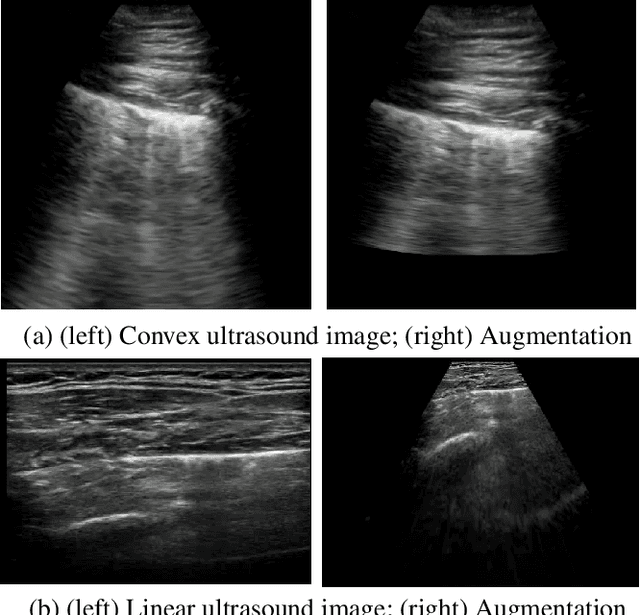

As the global population continues to face significant negative impact by the on-going COVID-19 pandemic, there has been an increasing usage of point-of-care ultrasound (POCUS) imaging as a low-cost and effective imaging modality of choice in the COVID-19 clinical workflow. A major barrier with widespread adoption of POCUS in the COVID-19 clinical workflow is the scarcity of expert clinicians that can interpret POCUS examinations, leading to considerable interest in deep learning-driven clinical decision support systems to tackle this challenge. A major challenge to building deep neural networks for COVID-19 screening using POCUS is the heterogeneity in the types of probes used to capture ultrasound images (e.g., convex vs. linear probes), which can lead to very different visual appearances. In this study, we explore the impact of leveraging extended linear-convex ultrasound augmentation learning on producing enhanced deep neural networks for COVID-19 assessment, where we conduct data augmentation on convex probe data alongside linear probe data that have been transformed to better resemble convex probe data. Experimental results using an efficient deep columnar anti-aliased convolutional neural network designed via a machined-driven design exploration strategy (which we name COVID-Net US-X) show that the proposed extended linear-convex ultrasound augmentation learning significantly increases performance, with a gain of 5.1% in test accuracy and 13.6% in AUC.